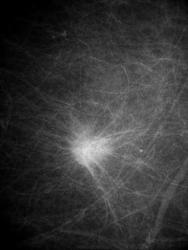

Женщина 55 лет. Самообращение. Вот такая шишечка, спаяна с кожей (симптом площадки и лимонной корки до 1.5 см в диаметре). Обследуется впервые. Направлена к онкологу.

Во-первых, это не инфильтративный рак, а классический узловой, с вовлечением кожи, т.к. близко к ней. Если присмотреться, видны держалки негатоскопа - это пленки. Аппарат Giotto (Италия), пленка маммографическая Kodak. Фото с негатоскопа, оцифровка в Фото эдитор онлайн.

Классическая картина, хоть в учебник.

Думаю, что коллега хотел сказать, что это не отёчно-инфильтративная форма рака, а узловая с инфильтративным ростом.

Слева подмышечный лимфоузел 3.5х2.5 см (край его виден на снимке).